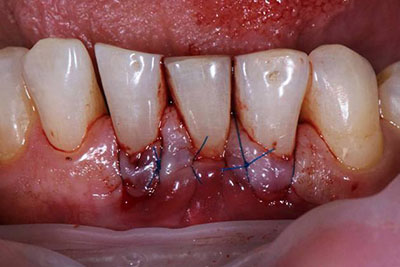

Хирургическое

Когда болезнь прогрессирует и купировать проблему медикаментами не удаётся, прибегают к хирургическому методу с использованием:

- Лоскутных операций. Десну разрезают у края, часть (лоскут) отодвигают в сторону, удаляют инфицированные ткани, тщательно обрабатывают корни зубов, костные карманы и внутреннюю поверхность лоскута. После ликвидации пародонтального кармана разрез зашивают.

В таких случаях приходится делать лоскутные операции для глубокой очистки, основная цель которых — ликвидация пародонтальных карманов. Выписываются противоотечные препараты и другие лекарства общего воздействия.